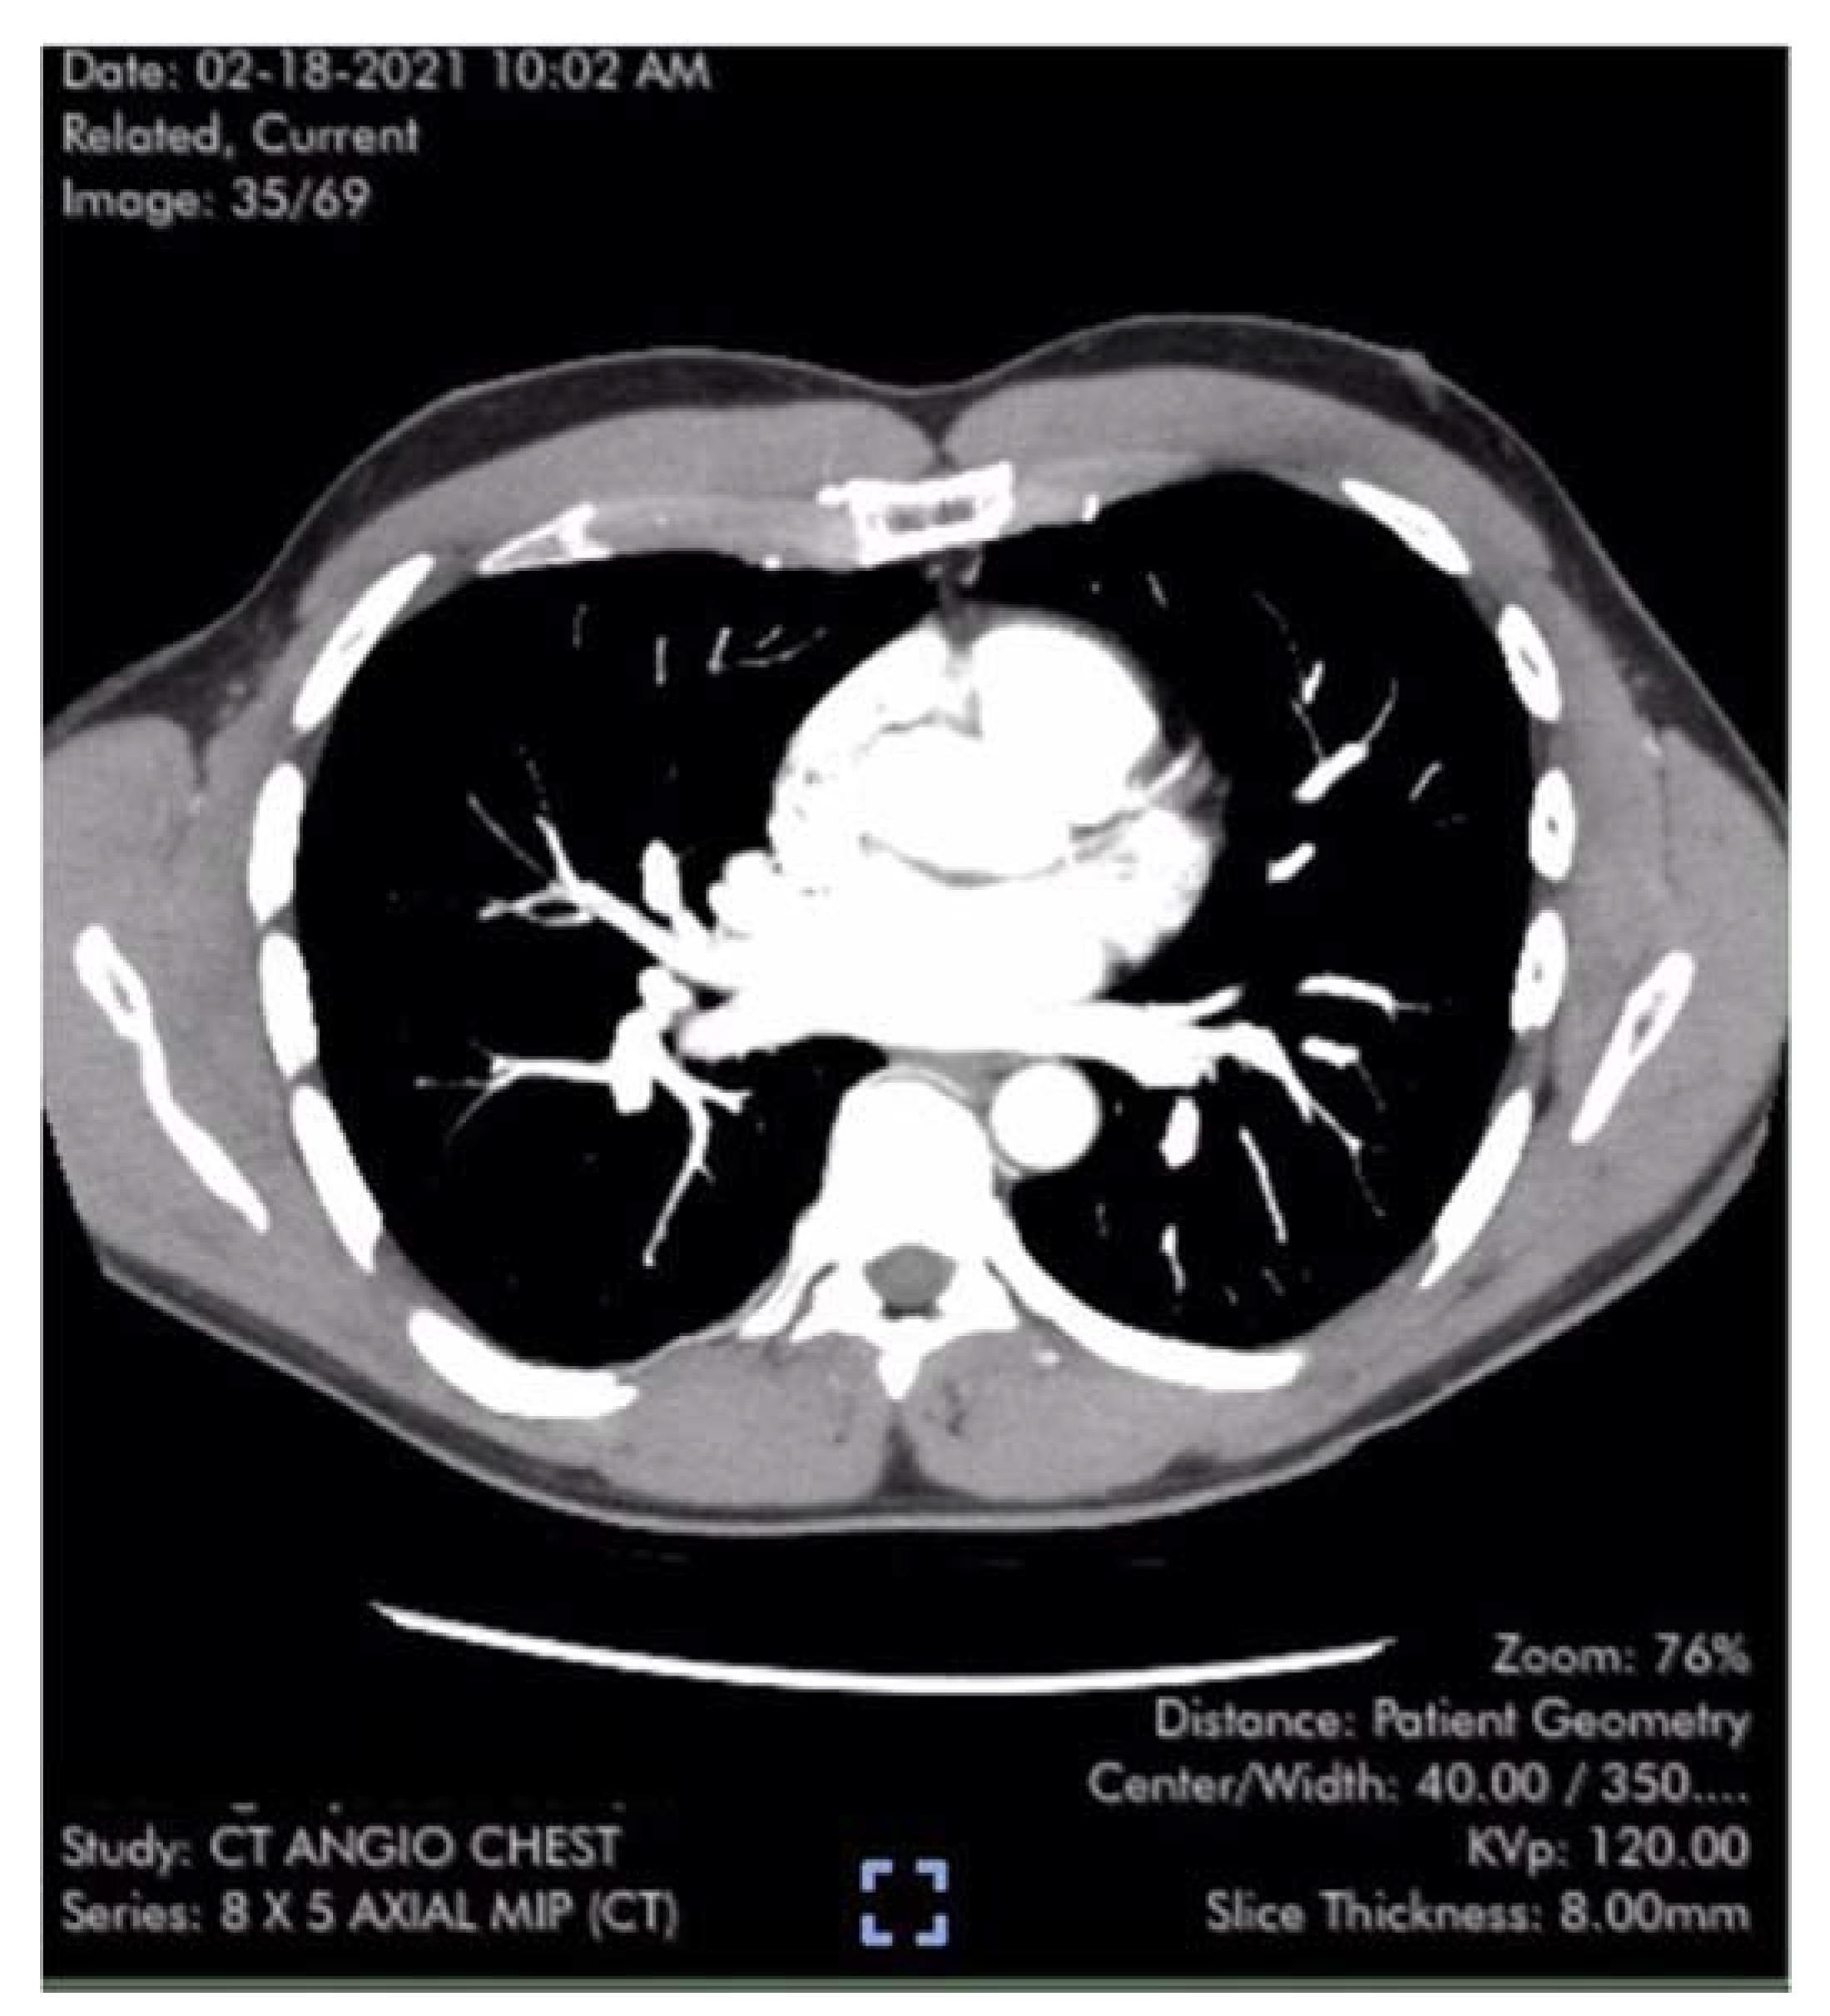

Case #1 is a previously healthy 49-year-old male physician athlete, body mass index (BMI) 23, non-smoker with a history of mild exercise-induced asthma treated with albuterol. Patient completed the primary series of Pfizer mRNA COVID-19 vaccine (BNT162b2) in January 2021. Approximately three weeks after the second dose patient suddenly developed severe fatigue, flu-like symptoms, tachycardia, palpitations, orthostasis, right-sided chest pressure and dyspnea on exertion. COVID PCR testing was negative. Transthoracic echocardiogram revealed normal left ventricular function with an ejection fraction (EF) of 65%, normal right ventricular size and function and a tricuspid regurgitation (TR) jet of 3.09 m/s (Figure 1). Estimated right ventricular systolic pressure (RVSP) of 42 mmHg was interpreted as mild/moderate pulmonary hypertension (Table 1). Laboratory studies including brain natriuretic peptide (BNP) 22 pg/ml (reference range <900 pg/ml) were unremarkable except for elevated low-density lipoprotein (LDL) cholesterol and hematocrit of 50%. Pulmonary computer tomography (CT) angiogram with 3D reconstruction of the PA tree was normal without evidence of pulmonary clots (Figure 2 and Figure 3). Patient subsequently developed 15 lbs of fluid gain and generalized swelling, neck pressure, headaches and a feeling of “being hung upside down” consistent with jugular vein distention (JVD) and cerebral venous congestion. The resting oxygen saturation (SpO2) was 92% and there was new onset systolic and diastolic arterial hypertension. Symptoms and chest pressure occurred at rest and were exacerbated by exertion. Exercise and functional limitations were consistent with New York Heart Association (NYHA) Class 3-4. Serial echocardiograms showed no worsening of RVSP and continued normal RV function (Table 1). Symptoms and exercise tolerance improved to NYHA class 1-2 over one year. Fluid weight gain, swelling, tachycardia and arterial hypertension resolved and the resting SpO2 increased to 98-100%. Flu-like symptoms and fatigue diminished but did not disappear. RVSP remained elevated and essentially unchanged by follow up echocardiography (Table 1).

Figure 1. Transthoracic Echocardiogram with measurement of TR velocity by continuous-wave Doppler. Pressure gradient derived from simplified Bernoulli Equation P=4v2.